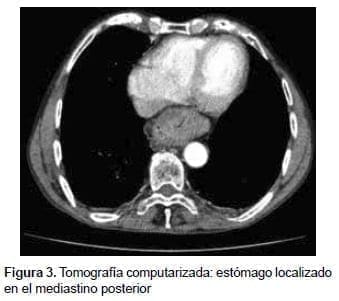

Se decidió ampliar el estudio con una tomografía computarizada (TC) de abdomen con contraste, en la cual se reportó una discreta dilatación esofágica en el tercio medio y proximal, acompañada de engrosamiento difuso de las paredes, y una hernia hiatal por deslizamiento con una porción del estómago ubicado en el mediastino posterior (figura 3).